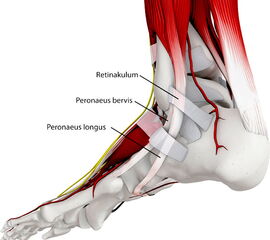

Anatomie

Verlauf der Peronealsehnen hinter der Fibula

Der anatomische Verlauf der Peronealsehnen spielt bei den meisten Erkrankungen eine zentrale Rolle.

Die Peroneus longus Sehne und die Peroneus brevis Sehne (wenn vorhanden auch die Peroneus quartus Sehne) verlaufen hinter der Fibula, um dann um die Außenknöchelspitze herum nach ventral zu ziehen. Die Länge des Muskels unterliegt einer großen anatomischen Variation, teilweise sind der Sehne noch distal der Fibulaspitze Muskelanteile angelagert. Zur Vermeidung einer Luxation über den Malleolus lateralis, gleiten die Sehnen in einer muldenförmigen Rinne im Bereich der dorsalen Fibula, zusätzlich werden die Sehnen durch das Retinaculum superior und das Retinaculum inferior stabilisiert 1.